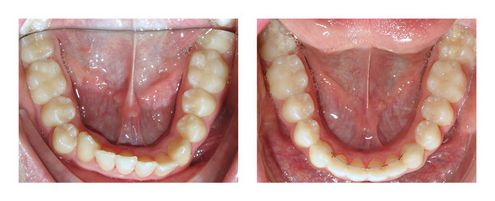

Cas 18 : Elargissement précoce des arcades pour gagner de la place

Ayant un visage parfaitement équilibré et les dents étant bien emboîtées, les arcades ont été légèrement élargies précocement pour gagner un peu de place. Une fois la place créée, les dents de devant ont été alignées avec un dispositif orthodontique fixe classique.

Le résultat a été obtenu en 1 an, mais a imposé après la phase active de traitement de porter des gouttières de maintien. En effet, ces corrections sont très récidivantes au début. Le but de ces traitements est d’éviter des extractions à l’adolescence.